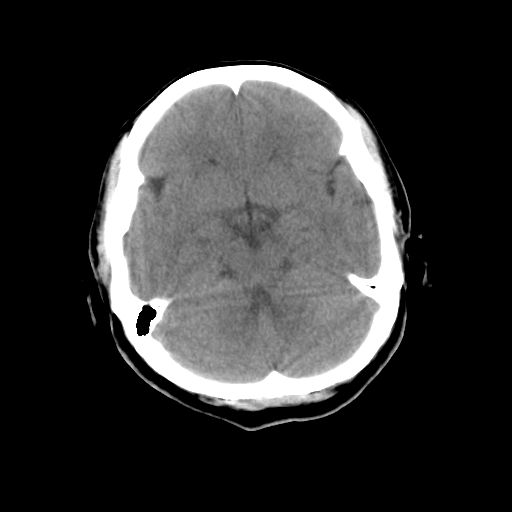

标题: CT23995:女,42岁,前额部外伤1小时,伤后头痛。

女,42岁,前额部外伤1小时,伤后头痛。

头颅ct平扫未见异常

颅脑ct平扫未见异常,必要时复查

未见明显外伤性改变。

左枕骨松质骨不均匀低密度灶,边缘清楚,考虑良性松质骨性骨瘤可能性大。